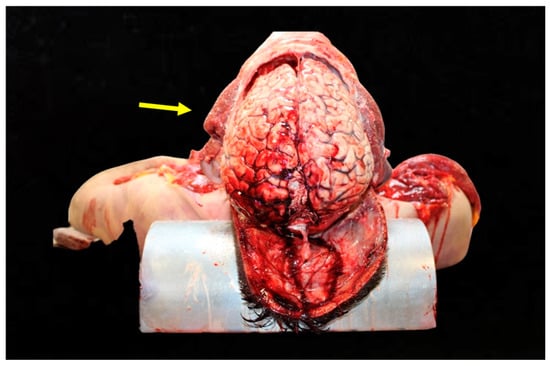

Figure 1. Analysis of head trauma in the frontal region. This image depicts significant bruising and lacerations on the frontal area of the skull. The external injuries suggest a high-energy impact consistent with head-on collisions.